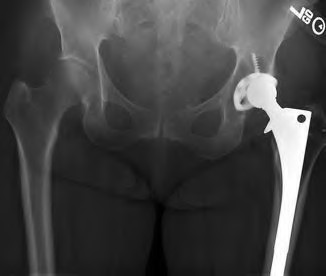

A 67-year-old man who underwent total hip arthroplasty (THA) 4 years ago fell on to his right hip. His pre-injury right hip film is seen in Figure A while films of his current injury are seen in Figures B and C. Prior to the fall he had no thigh or hip pain. His ESR and CRP are within normal limits. During intraoperative assessment, the acetabular and femoral stems are found to be well fixed. What is the next best course of action?

This patient has a periprosthetic hip fracture at the level of the stem with a stable prosthesis, indicated open reduction and internal fixation as the treatment of choice.

The Vancouver Classification can be helpful in clinical decision-making regarding fixation versus revision of periprosthetic hip fractures of the proximal femur. A stable implant, by nature, does not need to be revised in the setting of adequate bone stock for fixation, but the ultimate test of stability should be in the operating room. Many fixation strategies are appropriate, but many implants include locking plate fixation for concerns of stress-shielded bone around the implant as well as use of unicortical fixation at the level of the stem.

Pike et al review the current trends in treating B1 fractures including locking plates with strut allografts, minimally invasive plate osteosynthesis (MIPO) and locking plates spanning femoral THA and TKA stems in selected patients. The authors conclude that no studies currently provide evidence establishing one

Illustration A shows a possible fixation construct for this patient's fracture. The Vancouver Classification is seen in Illustration B and Illustration C represents an algorithm for treatment options.